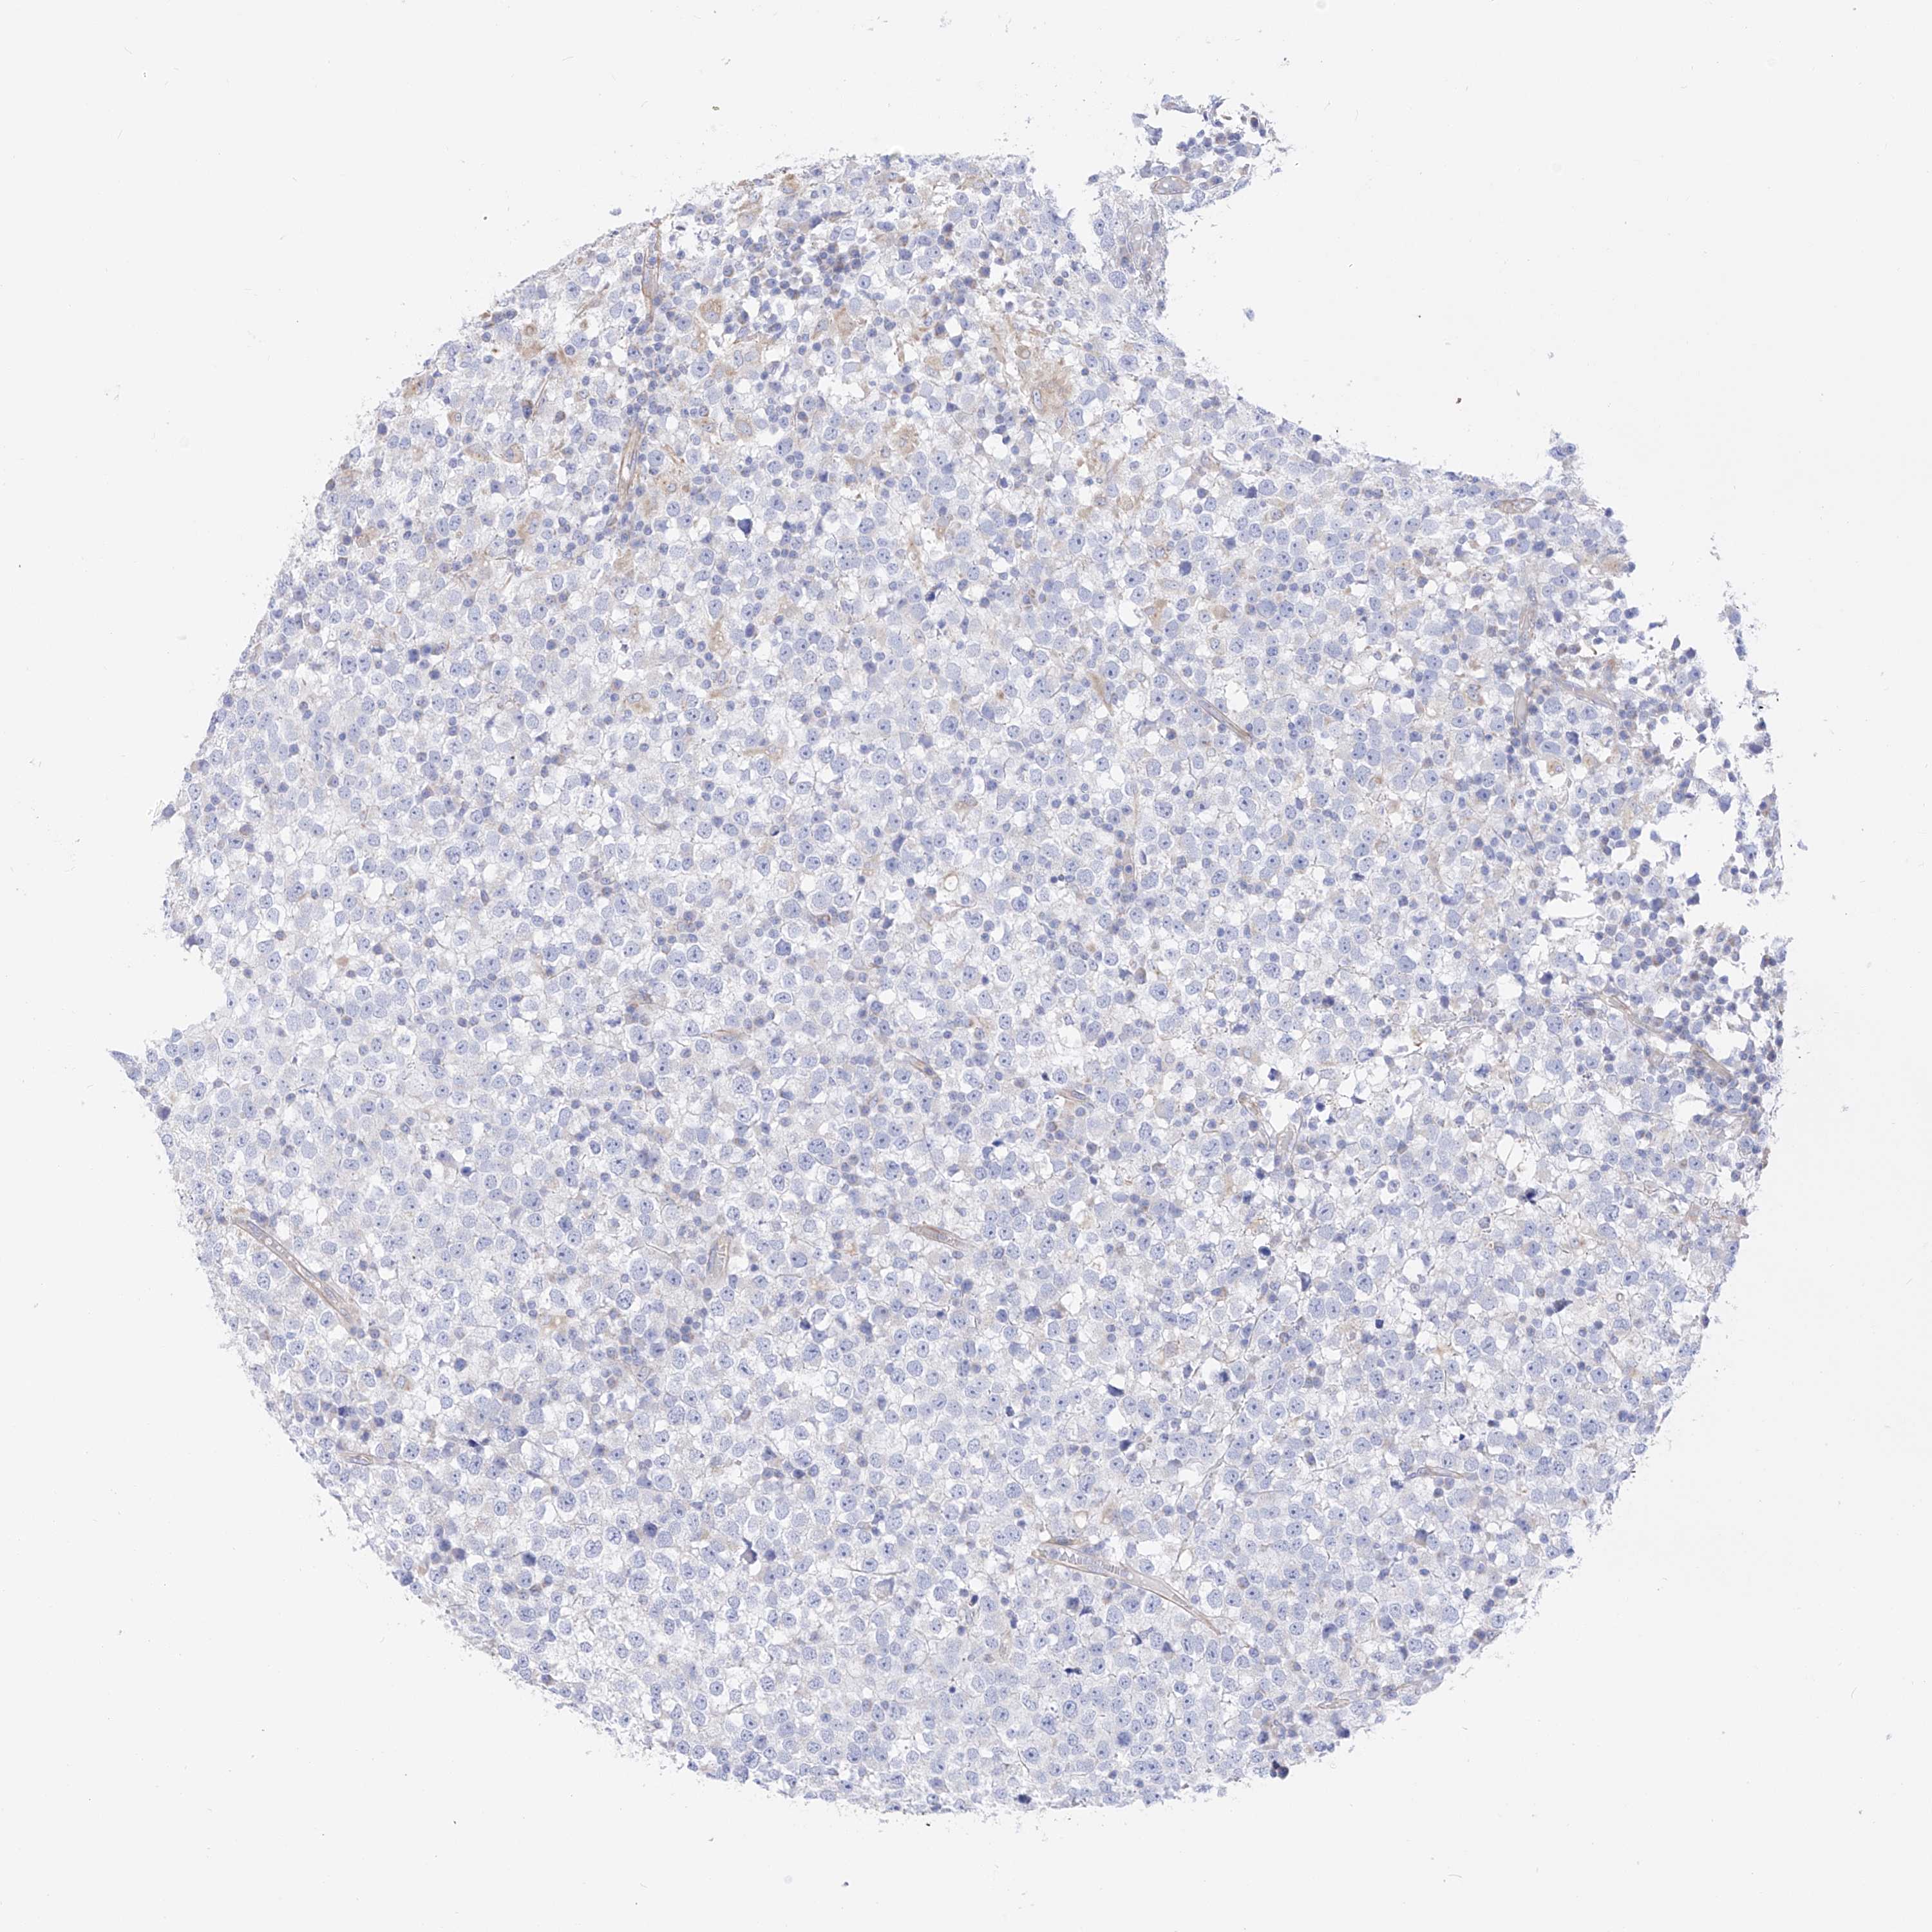

TESTIS CANCER - Protein expressioni

A mouse-over function shows sample information and annotation data. Click on an image to view it in a full screen mode. Samples can be filtered based on level of antibody staining by selecting one or several of the following categories: high, medium, low and not detected. The assay and annotation is described here.

Note that samples used for immunohistochemistry by the Human Protein Atlas do not correspond to samples in the TCGA dataset.

Antibody stainingi

Antibody staining in the annotated cell types in the current human tissue is reported as not detected, low, medium, or high, based on conventional immunohistochemistry profiling in selected tissues. This score is based on the combination of the staining intensity and fraction of stained cells.

Each image is clickable and will lead to virtual microscopy that enables deeper exploration of all samples and also displays staining intensity scores, fraction scores and subcellular localization as well as patient and tissue information for each sample.

Antibody HPA030188

Antibody HPA030189

Antibody CAB002210

Carcinoma, Embryonal, NOS

Seminoma, NOS